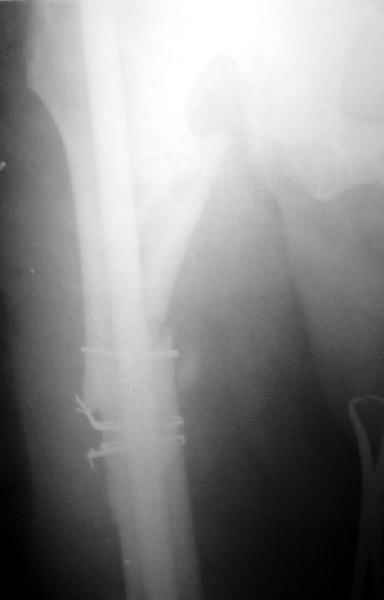

До нашей операции не ходил в связи с ложным суставом костей правой голени и шейки левого бедра.

После наших операций, не смотря на стимуляцию регенерации костной мозоли медикаментозной (остеогенон, кальций Д3, мумиё, фитин) терапией и введением в зону перелома алоэ с аутокровью элементы срастания в динамике очень слабые.

На данный момент правая голень срослась, больной активен в пределах постели. Второе(правое) бедро стабилизированное (рис. до и после). движения в коленном суставе: сгибательная контрактура правого коленного сустава 90, левого 145.

Наверное, мы привыкли, что штифт должен сидеть в костномозговом канале плотно. Гвоздь же этот, сидит относительно свободно, и это нас настораживает, не будет ли микроподвижность которая приведет к рецидиву ложного сустава.